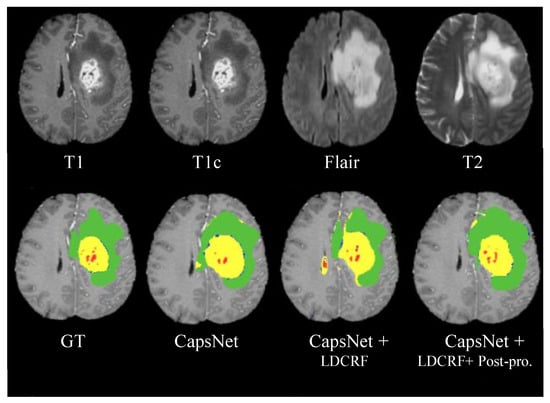

| Methods | Dice | Sensitivity | Specificity | ||||||

|---|---|---|---|---|---|---|---|---|---|

| Complete | Core | Enhancing | Complete | Core | Enhancing | Complete | Core | Enhancing | |

| CapsNet | 0.82 | 0.80 | 0.81 | 0.79 | 0.76 | 0.78 | 0.86 | 0.84 | 0.82 |

| CapsNet + LDCRF | 0.87 | 0.84 | 0.82 | 0.85 | 0.82 | 0.80 | 0.88 | 0.86 | 0.83 |

| CapsNet + LDCRF + Post-processing | 0.91 | 0.86 | 0.85 | 0.88 | 0.84 | 0.83 | 0.93 | 0.90 | 0.86 |

| Methods | Dice | ||

|---|---|---|---|

| Complete | Core | Enhancing | |

| Kuan-Lun Tseng et al. [33] (DCNN) | 0.85 | 0.68 | 0.87 |

| L. L. Folgoc et al. [7] (CLDF) | 0.79 | 0.67 | 0.70 |

| A. R. P. Piedra et al. [34] (VCTB) | 0.74 | 0.54 | 0.54 |

| Bi Song et al. [35] (AG) | 0.85 | 0.70 | 0.73 |

| C. Adria et al. [36] (3DNeT3) | 0.92 | 0.84 | 0.77 |

| S. Hussain et al. [32] (ILinear) | 0.86 | 0.87 | 0.90 |

| Our Method | 0.91 | 0.86 | 0.85 |